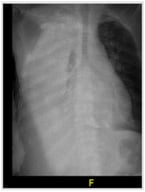

Background: Severe Acute Respiratory Syndrome Coronavirus 2 (SARS-CoV-2) can cause persistent, multisystem complications collectively termed long COVID. Cardiovascular sequelae are among the most clinically significant yet remain incompletely characterized. This review aimed to synthesize current evidence on objective cardiovascular outcomes in long COVID and explore underlying mechanisms. Methods: A systematic review was conducted using PubMed, Scopus, and Web of Science for studies published between January 2020 and March 2024. Search terms included “COVID-19,” “long COVID,” “post-acute sequelae,” “cardiovascular,” “echocardiography,” “biomarkers,” and “imaging.” Only studies reporting at least one cardiovascular outcome, defined as either objectively measured parameters (e.g., echocardiography, cardiac biomarkers, ECG findings, or vascular function indices) or clinically relevant cardiovascular symptoms during follow-up, were included. From 412 identified records, ten recent, high-quality studies with a primary cardiovascular focus were selected. This systematic review was conducted in accordance with the PRISMA 2020 guidelines. Results: Long COVID is associated with subclinical myocardial dysfunction, arrhythmias, endothelial injury, vascular stiffness, and a prothrombotic state. Reported findings included reduced left ventricular ejection fraction, impaired global longitudinal strain, increased arterial stiffness, elevated cardiac biomarkers, new-onset hypertension, and persistent ECG changes, even in non-hospitalized patients without prior cardiovascular disease. Proposed mechanisms include myocardial inflammation, endothelial dysfunction, renin–angiotensin–aldosterone system dysregulation, autonomic imbalance, and chronic inflammation. Secondary bacterial and fungal infections were noted in critically ill survivors but did not fully explain the breadth or persistence of symptoms. Conclusions: Long COVID is a heterogeneous entity with substantial cardiovascular implications across all levels of acute disease severity. Early detection through longitudinal monitoring, standardized definitions, and multidisciplinary care is essential to reduce long-term cardiovascular risk.